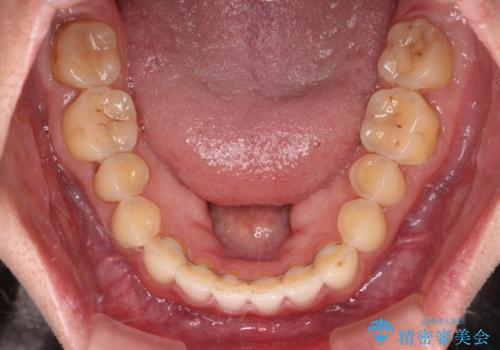

すきっ歯はあっという間に後戻りを起こすので、可及的に後戻りを防止するために、上下前歯部を舌側からワイヤーで固定しています。

通常は下顎前歯のみに行っていますが、空隙歯列弓では上顎でも行っています。